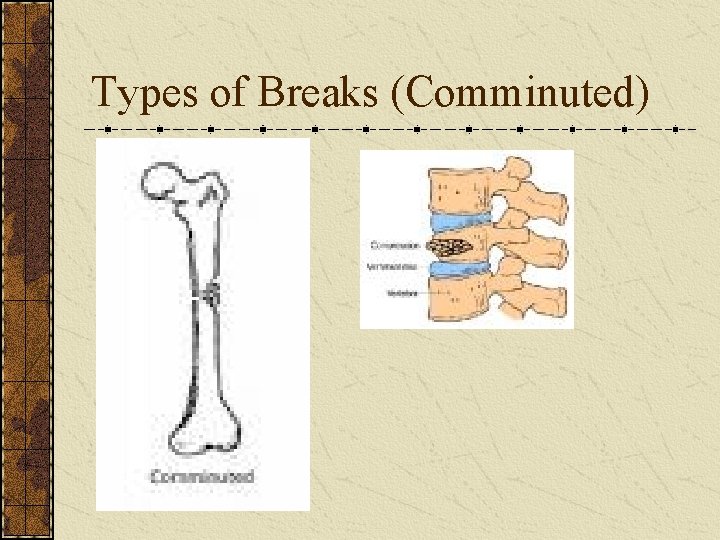

Types of Breaks There are five different types of fracture: 1. Transverse: Straight across bone 2. Oblique: Diagonal break across bone 3. Spiral: Around the bone 4. Comminuted: Bone is shattered 5. Greenstick: Bone breaks like a stick

Types of Breaks (Comminuted)